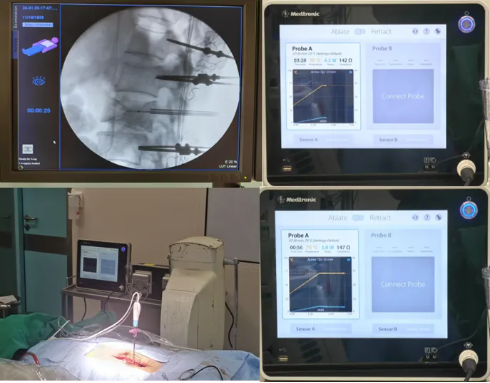

典型案例二

局麻下瘤样病损射频消融手术

·患者陆某某,男,42岁,因反复腰背部疼痛1年余入院。腰背痛VAS评分6分。

·诊断:腰2椎体痛性血管瘤

首例局麻下智能控温射频消融治疗椎体痛性血管瘤

患者手术全程保持清醒,射频消融过程中无任何不适。术后第一天佩戴腰围起床活动。术后腰背痛VAS评分3分。